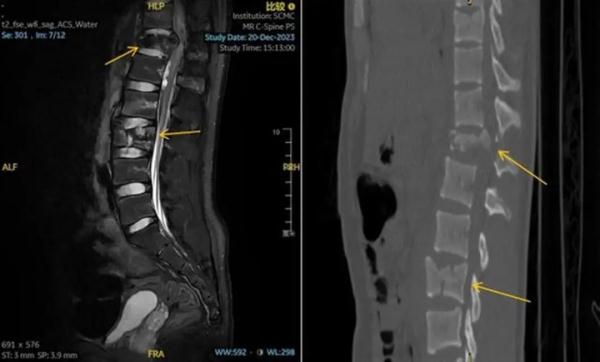

当时他虽意识清醒,但双下肢已无法站立,感觉麻痹。家属立即拨打120将孩子送至上海交通大学医学院附属上海儿童医学中心急诊。入院后,CT结果提示其胸、腰椎多发爆裂骨折,情况十分危急。

术前CT显示,孟迪的胸、腰椎多发爆裂性骨折伴移位(图源:上海儿童医学中心)